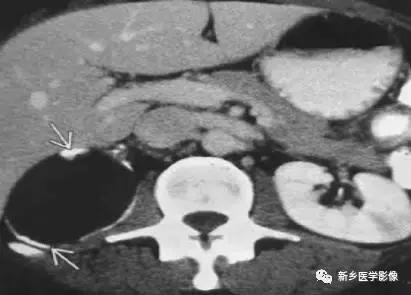

肾脏肿瘤

主要包括合并钙化的常见肿瘤或肿瘤样病变,如:肾囊肿,肾细胞癌,多房囊性肾瘤,多囊肝多囊肾囊壁钙化,肾脏结核,肾脏钙乳症